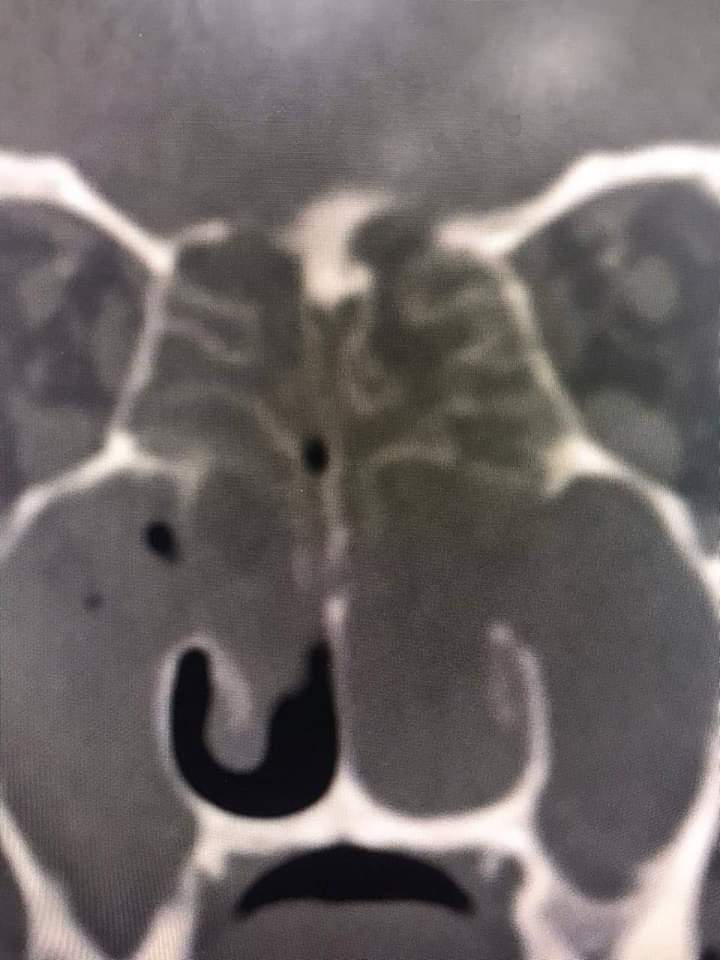

قام فريق طبي من دائرة الأذنية في الخدمات الطبية الملكية برئاسة العقيد الطبيب نبيل الشواقفة مستشار جراحة الأنف وقاع الجمجمة بإجراء عملية تنظير معقدة ونادرة لشاب يبلغ من العمر ٢٠ عاما، يعاني من التهاب فطري حاد ممتد إلى قاع الدماغ وحجرة العين مع وجود ثقب في قاع الجمجمة.

وبين الشواقفة ان المريض عندما راجع عيادة الأنف والأذن والحنجرة في مدينة الحسين الطبية كان يشكو من صداع شديد وانسداد في الأنف وصعوبة في التنفس، وبعد إجراء الفحص السريري والشعاعي تبين وجود إلتهاب حاد ممتد إلى قاع الجمجمة وحجرة العين وثقب في قاع الجمجمة، تقرر على أثرها إجراء العملية التي تعتبر من العمليات النادرة والمعقدة التي تحتاج فريق طبي متخصص .